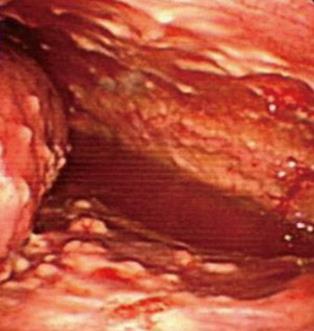

肺癌胸膜腔内转移造成恶性胸腔积液